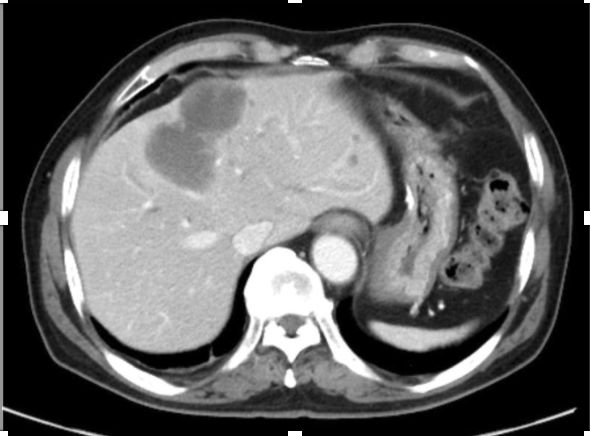

多形性平滑肌肉瘤占平滑肌肉瘤的10%, PLMS通常由老年人的骨骼肌或腹膜后组织起源,预后非常差,具有高度侵袭性。原发性肝PLMS非常罕见,占肝脏所有恶性肿瘤的0.5-2%。这例case报道的是既往诊断GIST,术后2年出现肝脏出现病灶,且在影像学考虑转移,形态非常符合GIST术后肝转移(如下图),而后并未对肝转移灶进行穿刺诊断,进行伊马替尼的治疗,在治疗无效后考虑是否存在原发耐药及其他肉瘤可能,进而进行手术治疗,术后病理组织学诊断PLMS明确。从这个病例汇报,我们可以看到,很多的肝脏的肉瘤在影像学表现相似,在治疗前,需要考虑既往病史的情况下,有必要进行穿刺再次明确病理,以区别一些相混淆的情况,另外对于耐药的转移性GIST患者而言,更要把握手术根治性切除的机会。